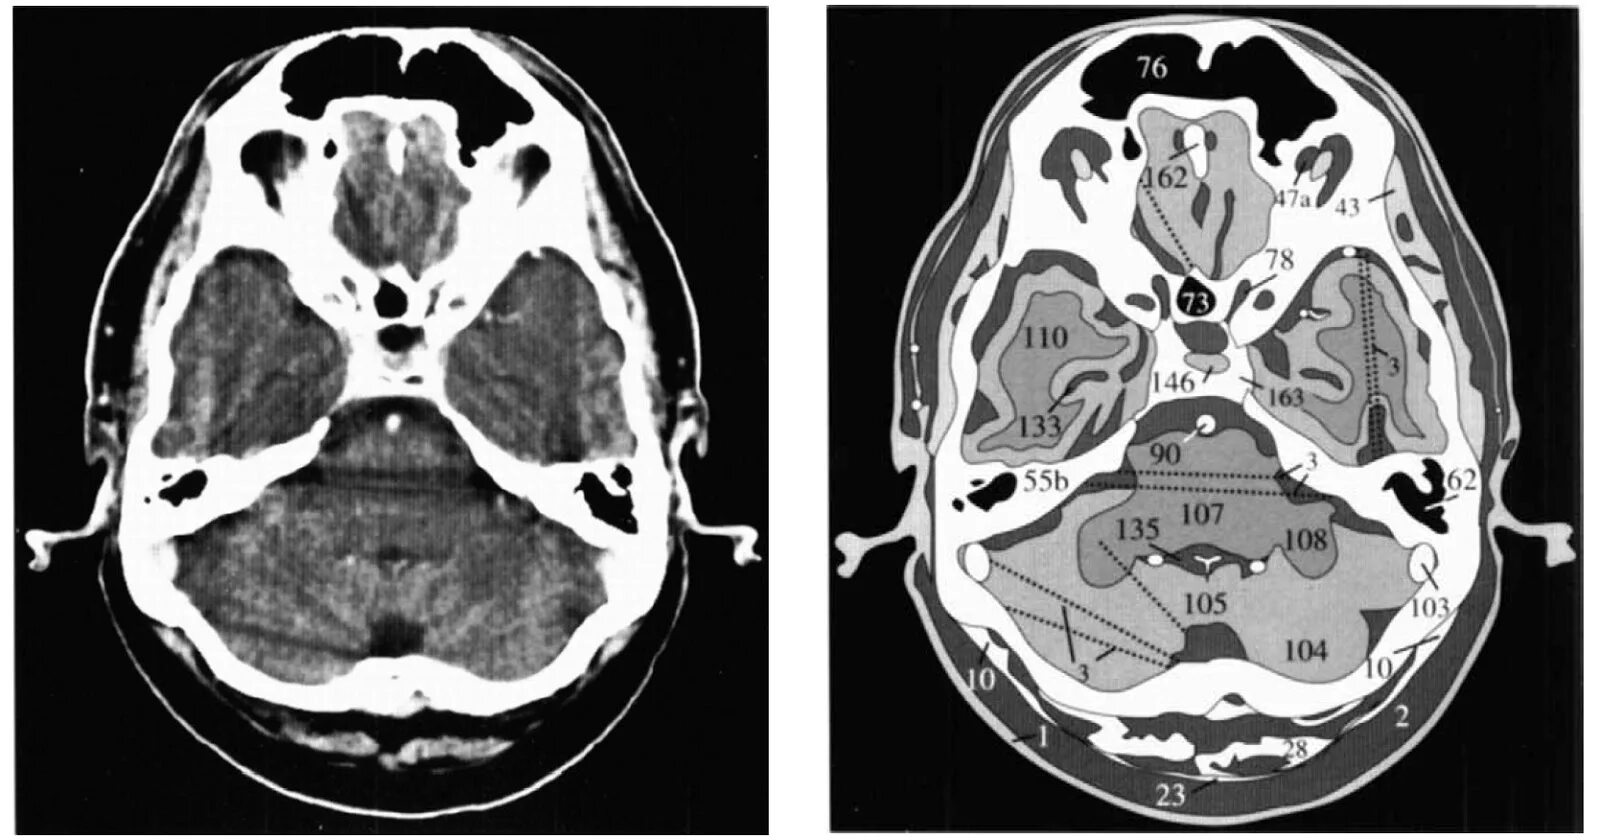

Какие виды кт